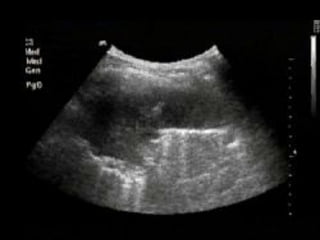

Tissue pattern representative of Alveolar

Consolidation

Tissue pattern representativeof Alveolar Consolidation Presence of hyperechoic punctiform imagesrepresentative of air bronchograms Pleural effusion Lower lobe